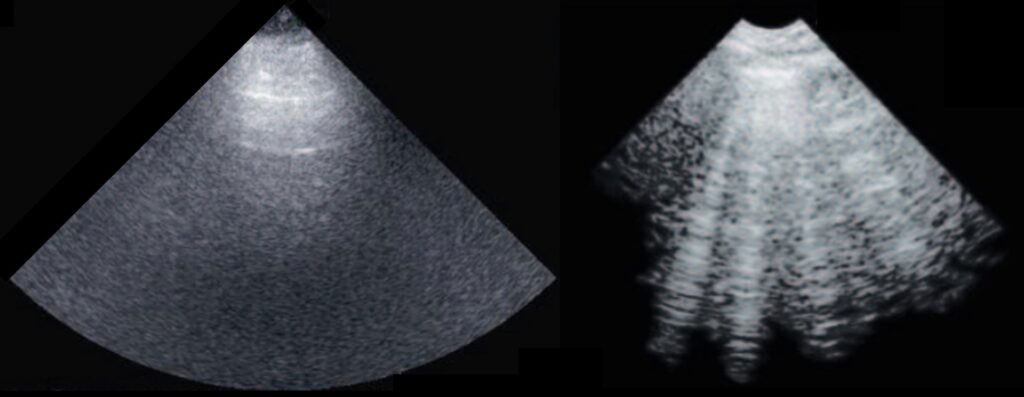

Interestingly, despite the fact that ultrasound virtually does not penetrate the lungs, reflecting from them due to a strong difference in the acoustic impedance of air and soft tissues, ultrasound images of diseased lungs (with pulmonary edema) differ significantly from those of healthy ones: vertical artifacts appear, called B-lines. However, the mechanism of B-line formation is not yet fully investigated, although its understanding is crucial for correct interpretation of lung ultrasound by physicians, as well as for the development of new methods of diagnostics.